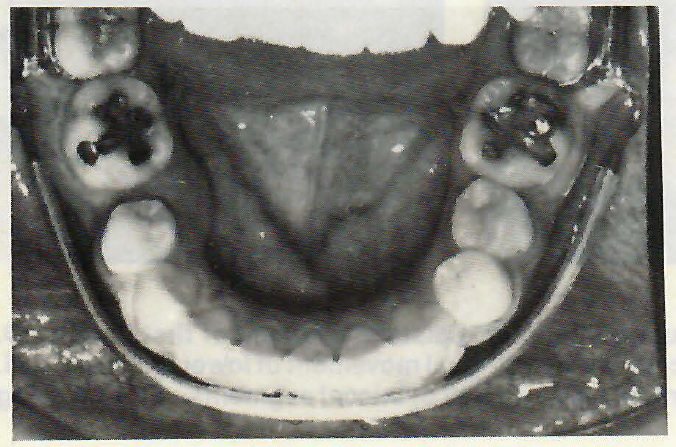

Fig. 3 Lip bumper